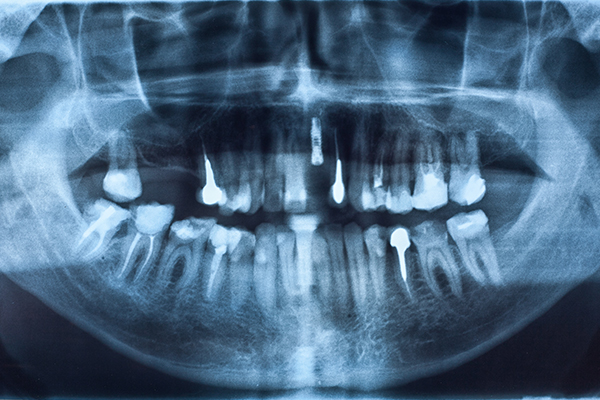

치주질환으로 인해 치조골이 약해지거나 소실이 심할 경우 임플란트 시술이 어려워 치조골 이식술이 동반 될 수 밖에 없습니다.

치조골 이식술이란 임플란트 시술부위에 치조골이 충분하지 못한 경우 환자의 자가골이나 인공뼈를 이식하여 뼈의 양을 늘린 후 임플란트를 식립하는 수술입니다.

치주 질환, 충치로 인해 치아를 상실한 경우

치조골이 부족하여 임플란트가 불가능한 경우

임플란트 실패나 부작용으로 인해 임플란트 재수술이 필요한 경우

치아를 상실한지 오래되었거나 장기간 틀니를 착용한 경우

임플란트를 식립힐 부위에 염증이 심할 경우